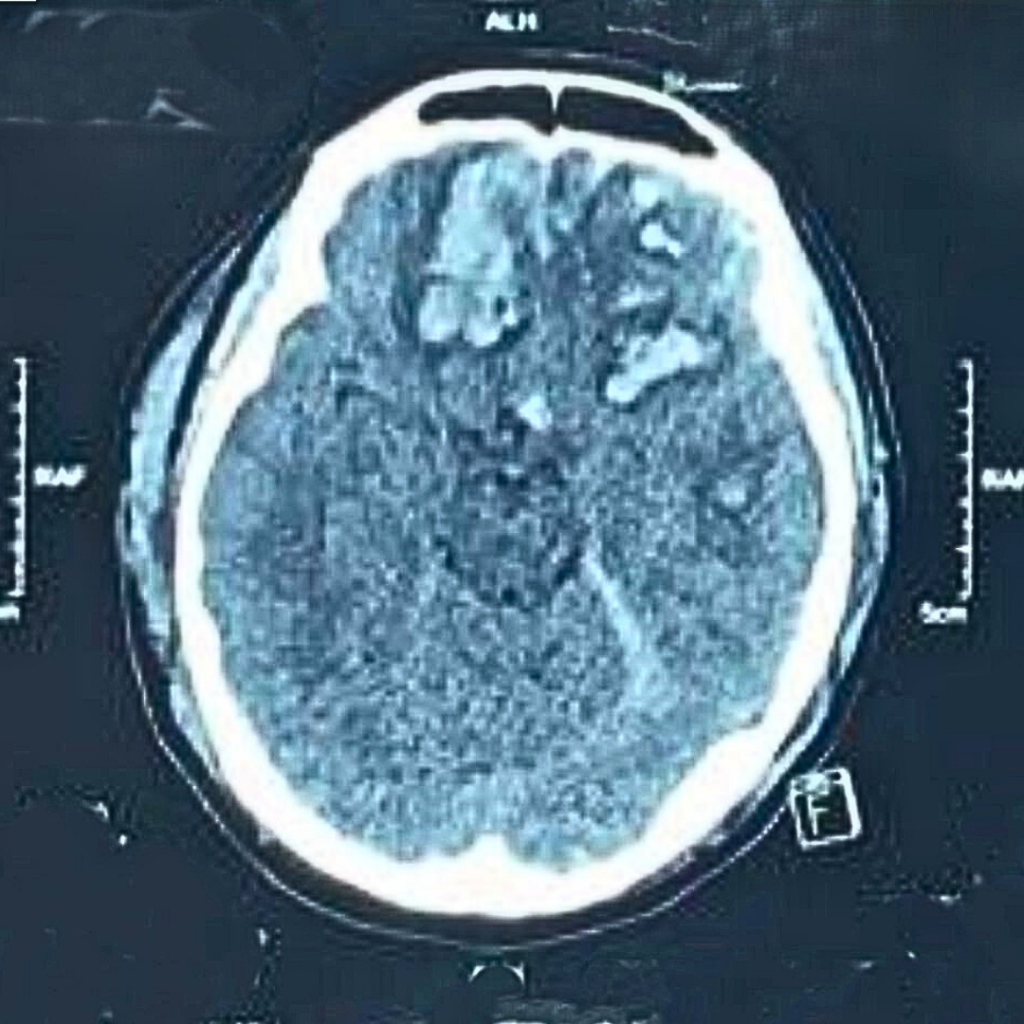

Menurut Dr. Low Siaw Nee, Pakar Bedah Saraf di SMCD, kecederaan seperti gegaran otak, pendarahan dalam tengkorak dan patah tengkorak adalah antara kes paling kerap ditemui. Dan penunggang motosikal kekal sebagai kumpulan paling berisiko mengalami pendarahan dalam tengkorak – jika dibandingkan dengam pemandu atau penumpang kereta.